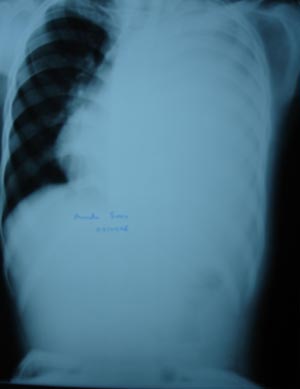

Massive pleural effusion

The radiological appearance of fluid in the pleural cavity are the same regardless of its eteiology whether it is transudate, exudates, pus or blood. The underlying lung pathology may not be seen because the pleural effusion shadow is uniform & homogenous. Whole left lung field shows ground glass opacity, with mediastinal & tracheal shift on opposite side. (patient responded very well to tapping & AKT)